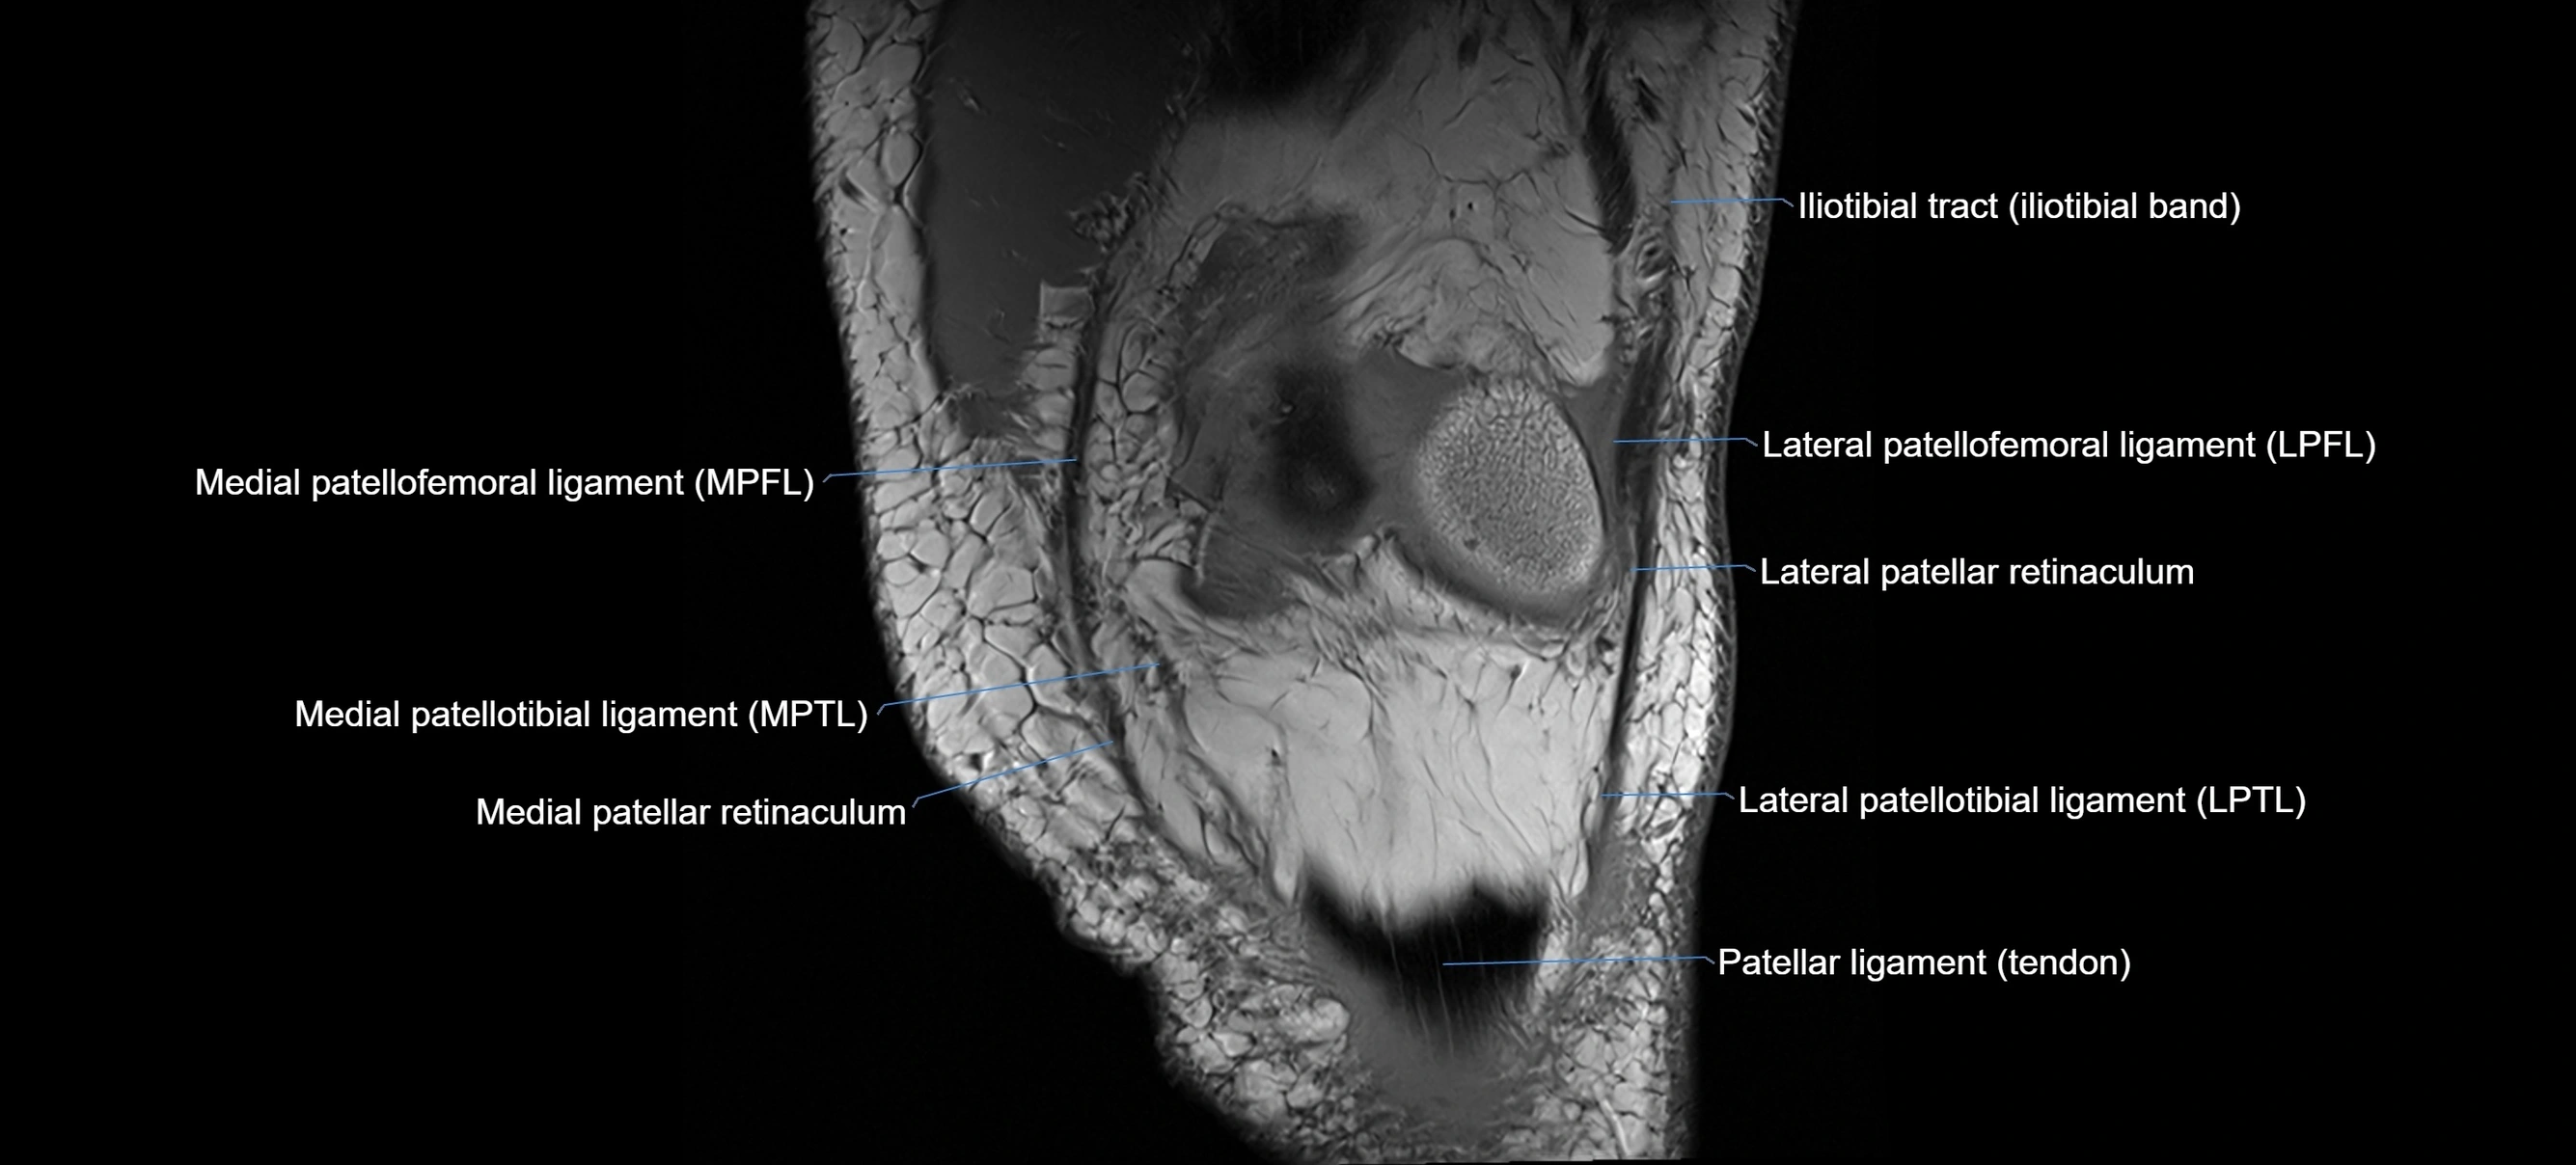

MRI images

image